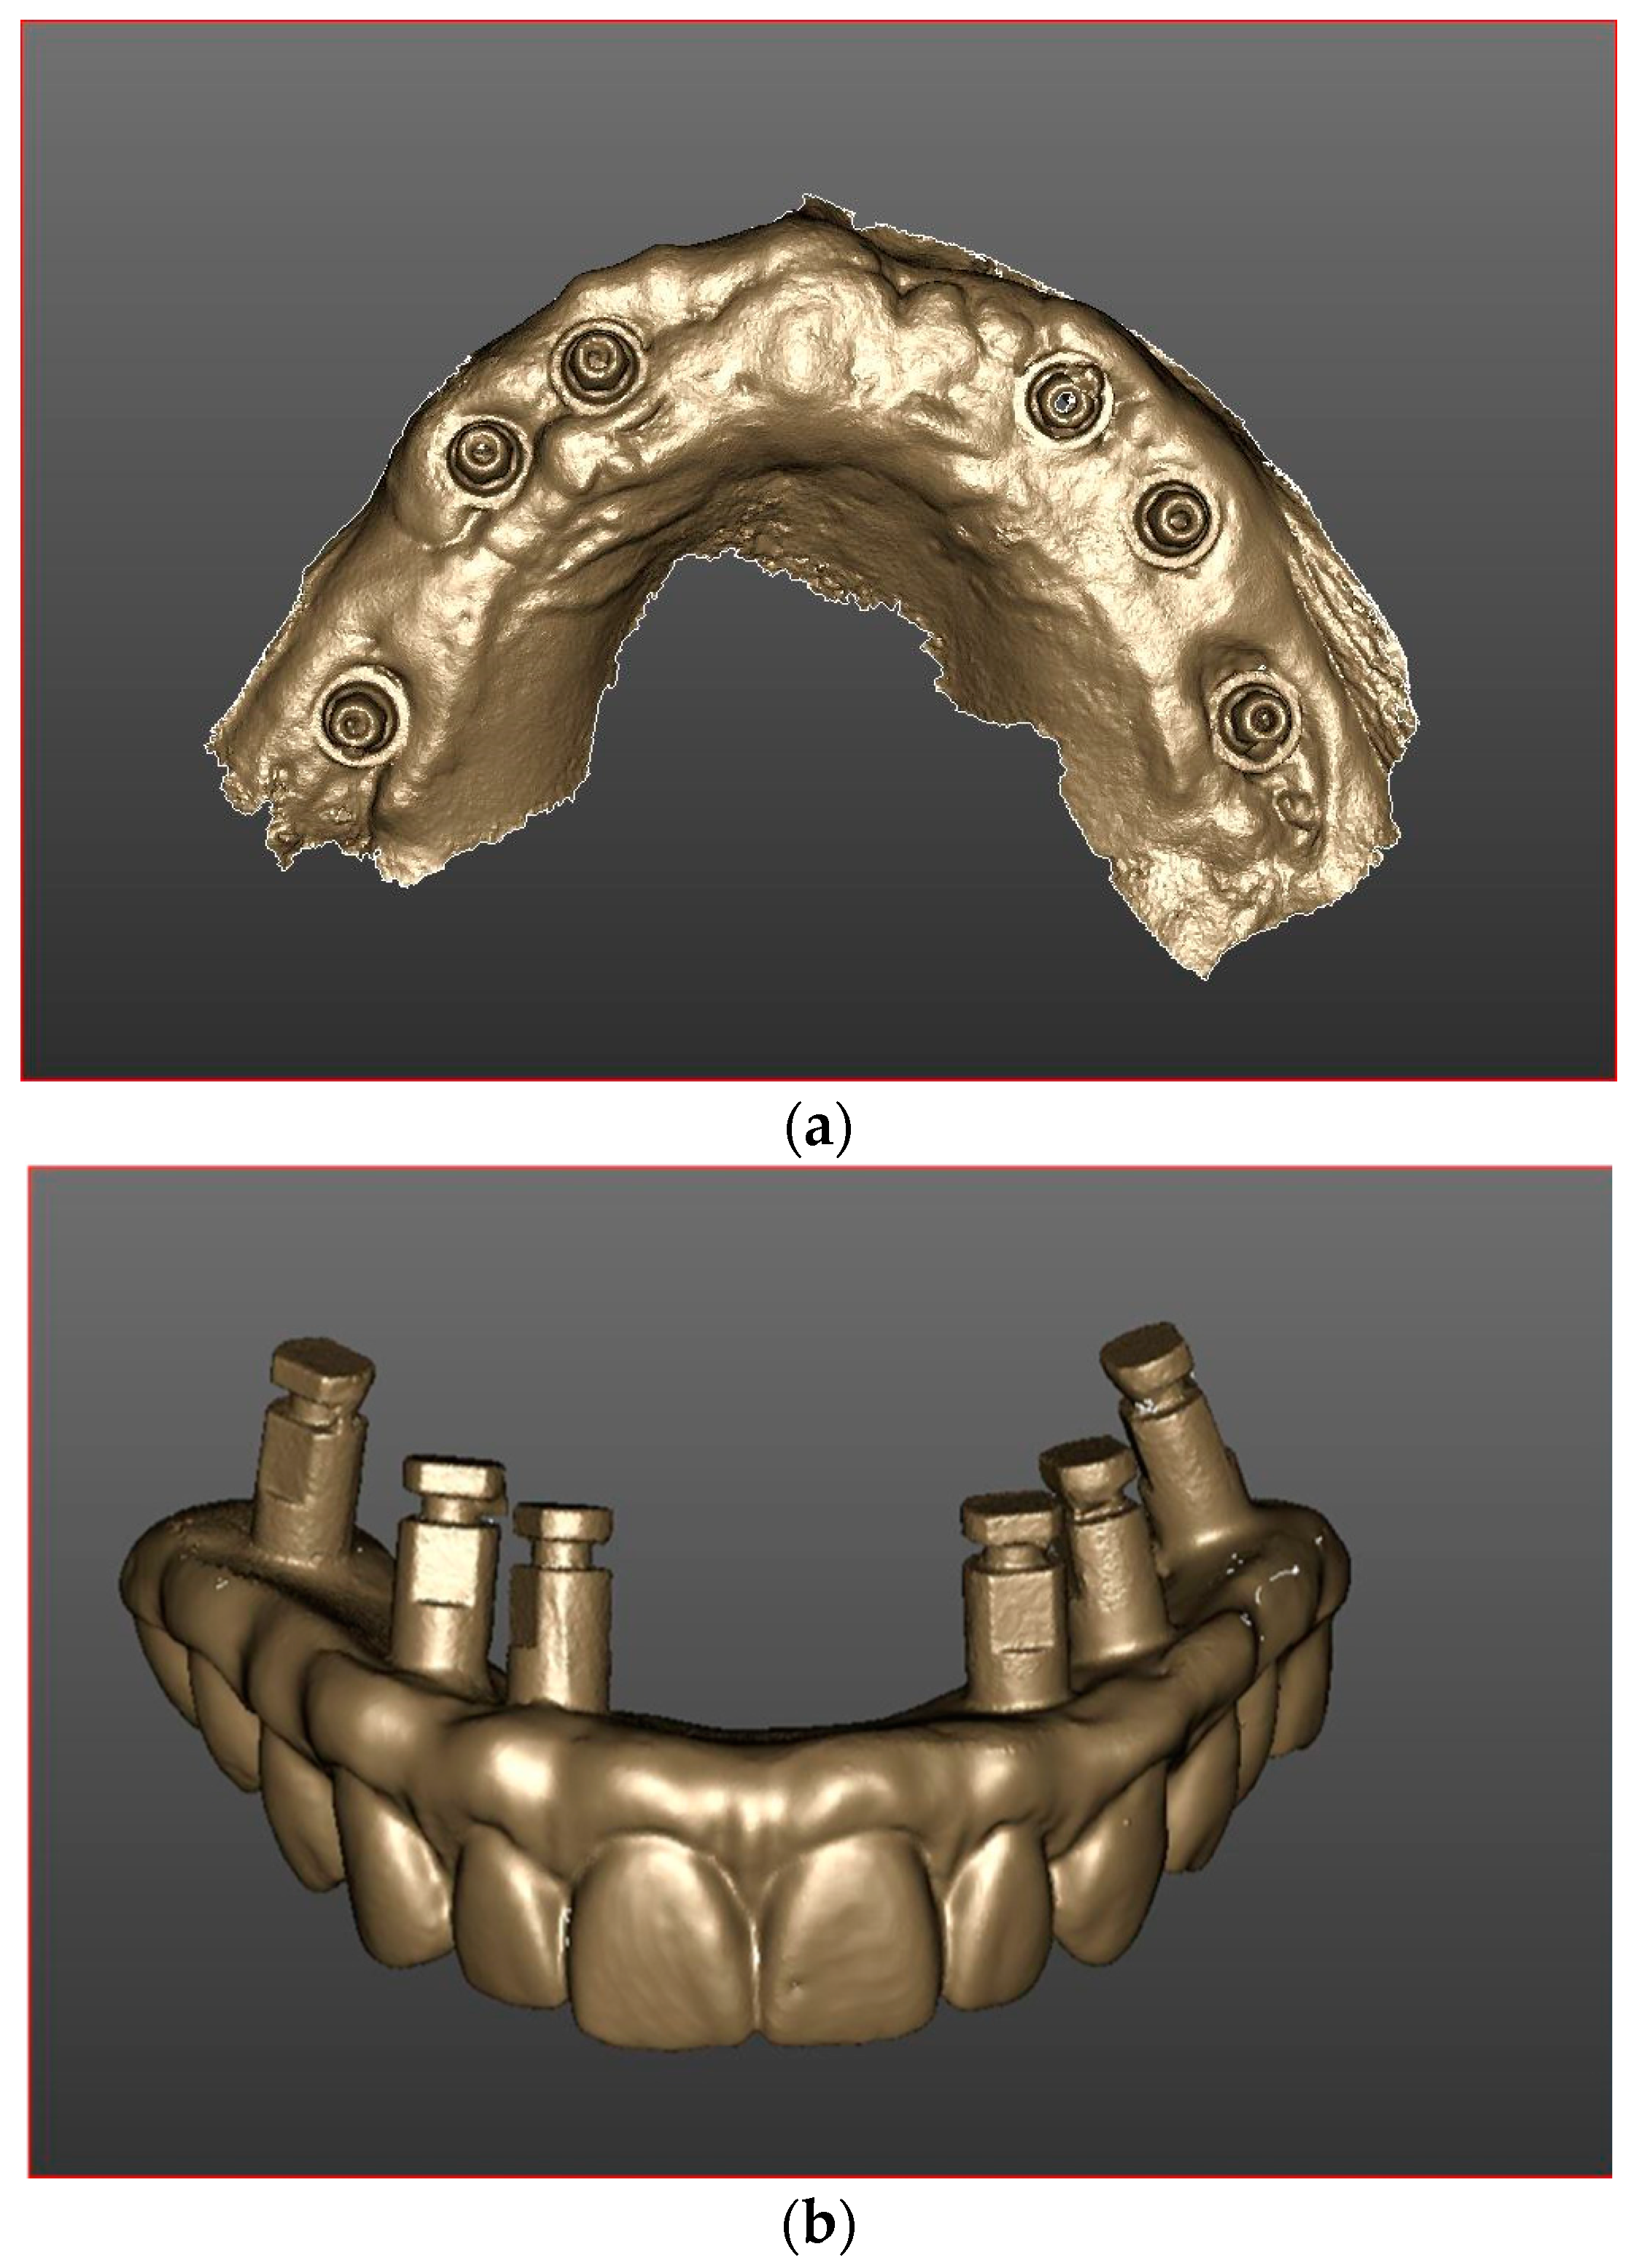

2. Materials and Methods

2.5. Prosthetic Protocol